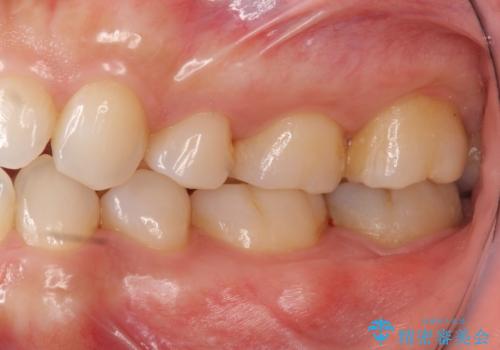

- 26万円(左下7:ジルコニアクラウン 10万円、仮歯 1万円、歯周外科手術(APF) 10万円、静脈内鎮静法 5万円)費用は治療当時の料金となります

他院で難しいと言われた虫歯治療をきっちりすることができて、とても喜んでいただきました。